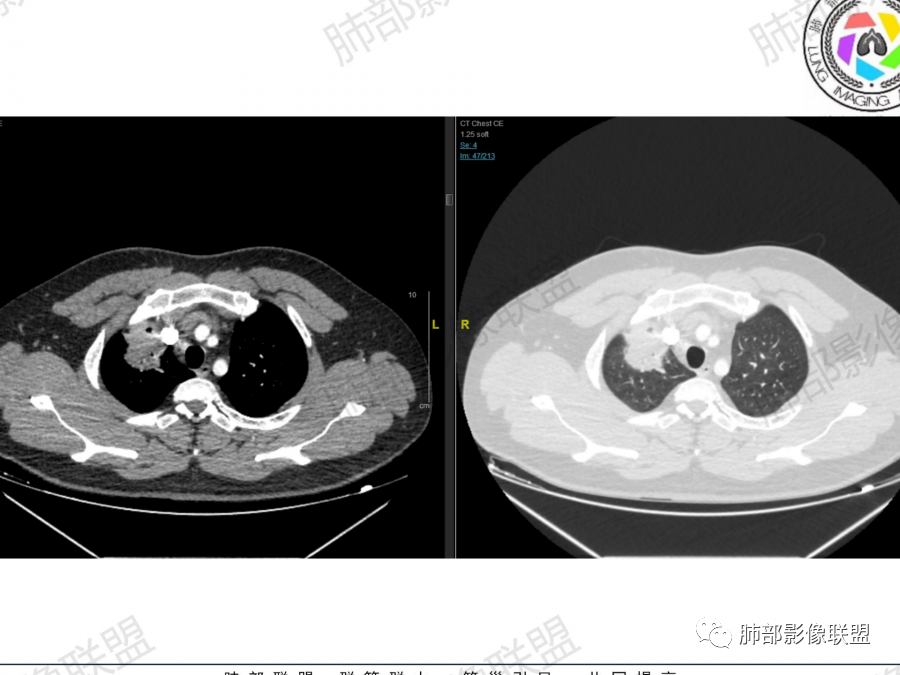

2、右肺多发结节影,大者位于右肺上叶尖段,内可见空洞,空洞内壁欠规整,内可见分隔,余结节位于胸膜下、结节大小不等、形态相近,强化均匀,内部可见血管穿行,血管及支气管走行自然。结合临床及影像,符合隐球病。

2、隐球菌感染有时相性,初期的隐球菌感染周围有晕征,晕从多变少,或包裹,或吸收,结节实性区可迅速变大,后期(慢性期)的隐球菌周围无明显晕征,边界较清楚。本例病变发病一月, 为后期,晕征不明显。

3、诊断隐球菌时,建议找卫星灶与“蘑菇兄弟”有一定价值,卫星灶可以在周围或在遥远的地方,在这里提一下隐球菌卫星灶距离的原因,隐球菌卫星灶常很远,推测:一次空气来源隐球菌感染进入双肺多处,部分定居繁殖;距离近的隐球菌“蘑菇兄弟”常常是二次感染。

总之,隐球菌卫星灶形态相似、可位于病变周围及远侧肺。与结核球的鉴别是:结核卫星灶、多形、多灶, 往往位于主病灶周围。本例卫星灶与“蘑菇兄弟”在右肺下叶,有提示作用。